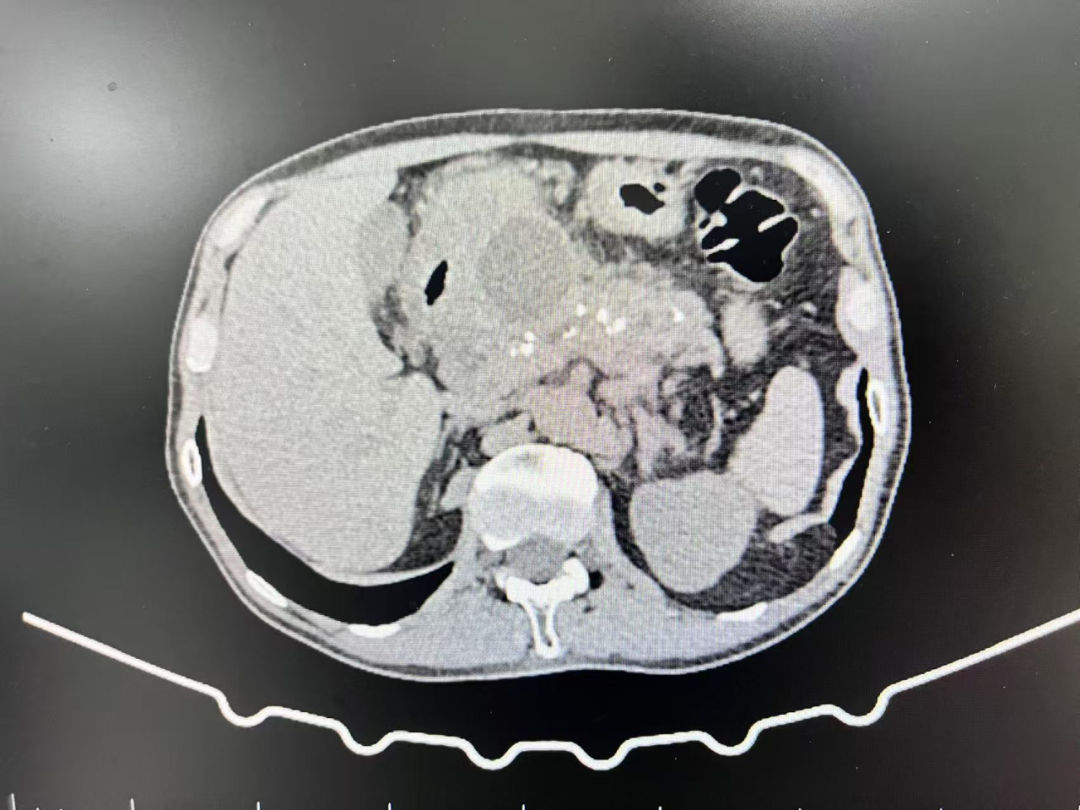

近日,51岁的王叔叔因腹痛呕吐3天入住我院消化内科,经完善相关检查后,磁共振【上腹部MRI平扫】提示:1.胰腺信号异常,多考虑:慢性胰腺炎急性发作。2.胰头颈区囊性病变,多考虑包裹性坏死。3.胰体囊性灶(囊腺瘤可能);【超声胃镜检查】提示:1.慢性胰腺炎,胰管多发结石2.胰头颈部囊性病灶(假性囊肿可能)3.浅表性胃窦炎